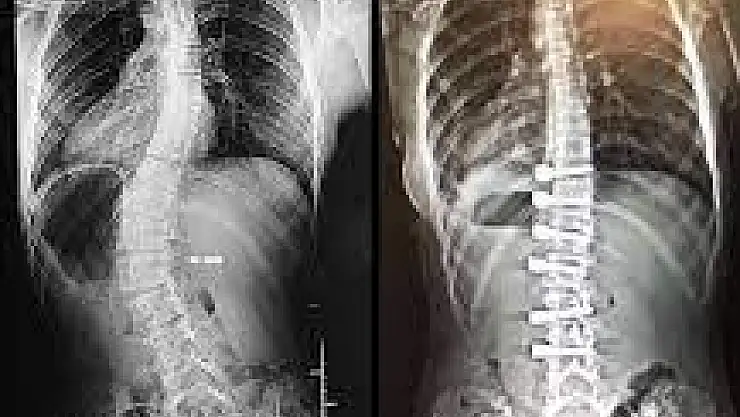

Omurilik ve Sinir Cerrahisi Uzmanı Opr. Dr. Ahmet Karkucak, skolyoz hastalığının nedenlerini, belirtilerini ve tedavi yöntemleri hakkında bilgiler verdi. Opr. Dr. Karkucak, "Skolyoz omurganın sevikal, trogal ve lomberde later dönüşleri ve rotasyonu ile seyreden omuriliğin kanal darlıklarına neden olabilen, iç organları özellikle akciğer ve kalp basılarına neden olabilen omurganın eğriliği olarak tarif edilebilecek bir hastalıktır. Kız çocuklarında ağırlıklı olarak daha sık bir şekilde görülen skolyoz, omurganın sağa ya da sol tarafa doğru eğilmesi neticesinde ortaya çıkan, kalça, göğüs kafesi ve kürek kemiklerini büyük oranda etkiler. Genellikle konzental olup altta yatan nedenler içinde omurganın gelişimi ile ilgili doğumsal efeklerin etki ettiği, patojenlerin beraber olabildiği bir omurga eğriliği durumudur. Sonradan olan omurga eğriliği skolyoz bu bir travma sonrası omurga da kemik kırıkları buna bağlı olarak değişiklikler olabilir” diye konuştu.

Skolyozun farklı sağlık sorunları oluşturabileceğini belirten Karkucak, “Omuzlardan birinin diğerine göre biraz daha yüksek olması yer alır. Omuzlar sağa ya da sola doğru kayma gösterebilir. Aynı durum bizzat kalça bölgesi için de geçerlidir. Bel girinti asimetrisi ve sırtta kaburgada yükseklik (çıkıntı) en önemli bulgularındandır. Öte yandan kürek kemiklerinin duruşunda da eşitlik açısından belli problemler ön plana çıkabilir. Skolyoz rahatsızlığına dair şüphe uyandıran bir bozukluk tespit edildiğinde vakit kaybetmeden bir hekime başvurulmalıdır. Skolyoz hangi aşamasında olursa olsun tedavi edilmediği takdirde çok daha başka sağlık sorunlarını beraberinde getirebilir” şeklinde konuştu.

“Erken tanı ve doğru tedavi seçimiyle skolyozun tam düzeltilmesi mümkündür. Tedavi ile yalnızca oluşan eğrilik düzeltilmez; bu eğriliğin neden olduğu şekil bozukluğuna bağlı olarak göğüs kafesinde meydana gelen hacim daralmasının da önüne geçilir. Skolyozda cerrahiye karar verilmeden önce en önemli etken skolyozun açısı, hastanın yaşı, genel durumu olarak görüntüsü, skolyoza bağlı olarak kalp, akciğer gibi solunum sıkıntısına neden olabilecek bası bulguları belirler. Burada tanı konulduktan sonra çok vakit kaybetmeden yakın takibe alıp önce egzersizler en önemli olan yüzme omurganın eğriliğini düzeltmek için tedaviye başlanmalıdır."